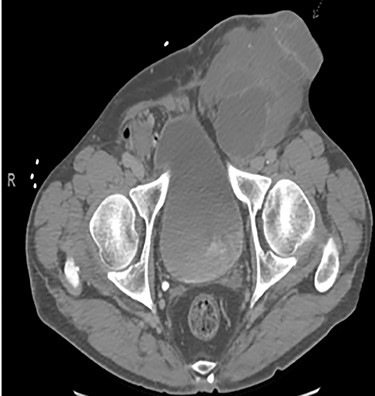

A 56-year-old male with a history of left testicular cancer treated with chemotherapy (Bleomycin, Etoposide, Cisplatin; BEP), radiotherapy, retroperitoneal lymph node dissection, and partial left nephrectomy in 1992 presented to hospital with complaints of left lower abdominal mass for 3–5 years, associated with ulceration and active drainage. He was asymptomatic with β-hCG and alpha-fetoprotein (AFP) levels within reference ranges (<2.39 and 1.4, respectively). On examination, inspection of abdomen revealed well-healed midline scar with bilateral incisional hernias and a 10 × 8 cm mass in the left lower quadrant (Fig. 1) firm and fixed to the abdominal wall. An open lesion characterized by yellow, non-purulent drainage was noted in the left lower quadrant. CT imaging of abdomen and pelvis with contrast revealed a multiloculated large cystic mass in the left inguinal canal measuring 11 × 7 × 7.7 cm (Fig. 2) along with a similar soft tissue nodule in the right inguinal area. A right retroperitoneal soft tissue mass in the mid abdomen was also identified, measuring 3.3 × 4.2 × 5.7 cm (Fig. 3). Changes of prior left nephrectomy and orchiectomy consistent with treatment of previous left-sided testicular cancer were also noted.

CT imaging abdomen and pelvis with contrast revealed a multiloculated large cystic mass in the left inguinal canal measuring 11 × 7 × 7.7 cm.